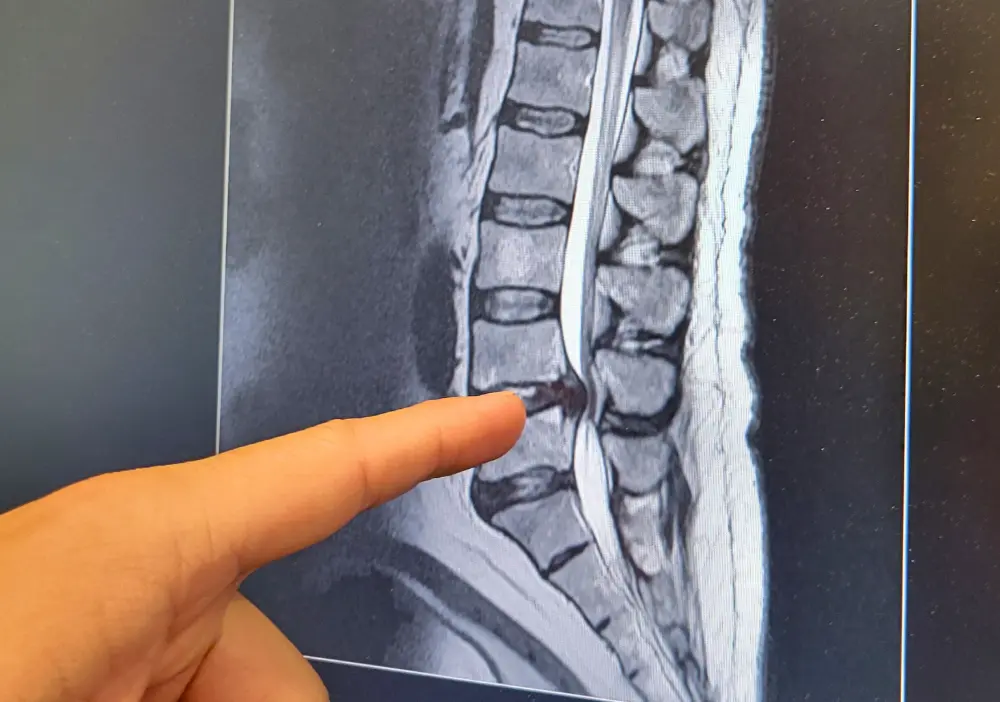

Your North Point Orthopaedics provider reviews your symptoms and examines your back to diagnose spinal stenosis. They typically have you move in certain ways, like leaning forward or backward, to determine how and when your symptoms intensify and lessen. Many people with spinal stenosis have less pain when bending forward. You may need imaging tests like X-rays, an MRI, or a CT scan to check for problems like disc degeneration, bone spurs, joint instability, and nerve compression. Your provider can use the information from these tests to plot a treatment course that gives you lasting pain relief.